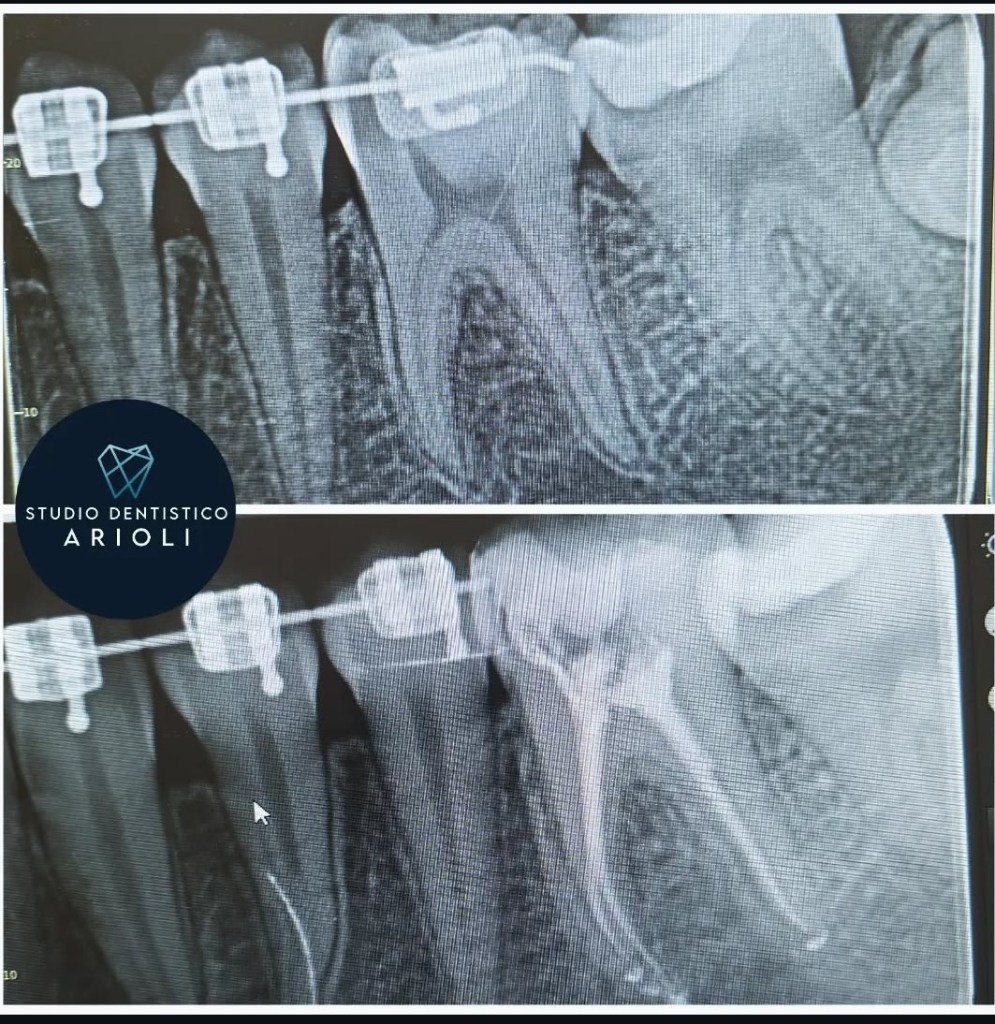

- controllo radiografico